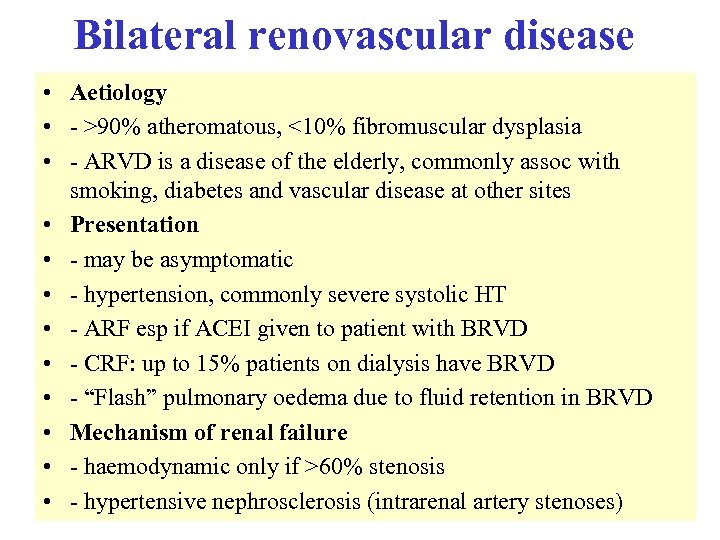

Bilateral renovascular disease • Aetiology • - >90% atheromatous, <10% fibromuscular dysplasia • - ARVD is a disease of the elderly, commonly assoc with smoking, diabetes and vascular disease at other sites • Presentation • - may be asymptomatic • - hypertension, commonly severe systolic HT • - ARF esp if ACEI given to patient with BRVD • - CRF: up to 15% patients on dialysis have BRVD • - “Flash” pulmonary oedema due to fluid retention in BRVD • Mechanism of renal failure • - haemodynamic only if >60% stenosis • - hypertensive nephrosclerosis (intrarenal artery stenoses)

Bilateral renovascular disease • Aetiology • - >90% atheromatous, <10% fibromuscular dysplasia • - ARVD is a disease of the elderly, commonly assoc with smoking, diabetes and vascular disease at other sites • Presentation • - may be asymptomatic • - hypertension, commonly severe systolic HT • - ARF esp if ACEI given to patient with BRVD • - CRF: up to 15% patients on dialysis have BRVD • - “Flash” pulmonary oedema due to fluid retention in BRVD • Mechanism of renal failure • - haemodynamic only if >60% stenosis • - hypertensive nephrosclerosis (intrarenal artery stenoses)